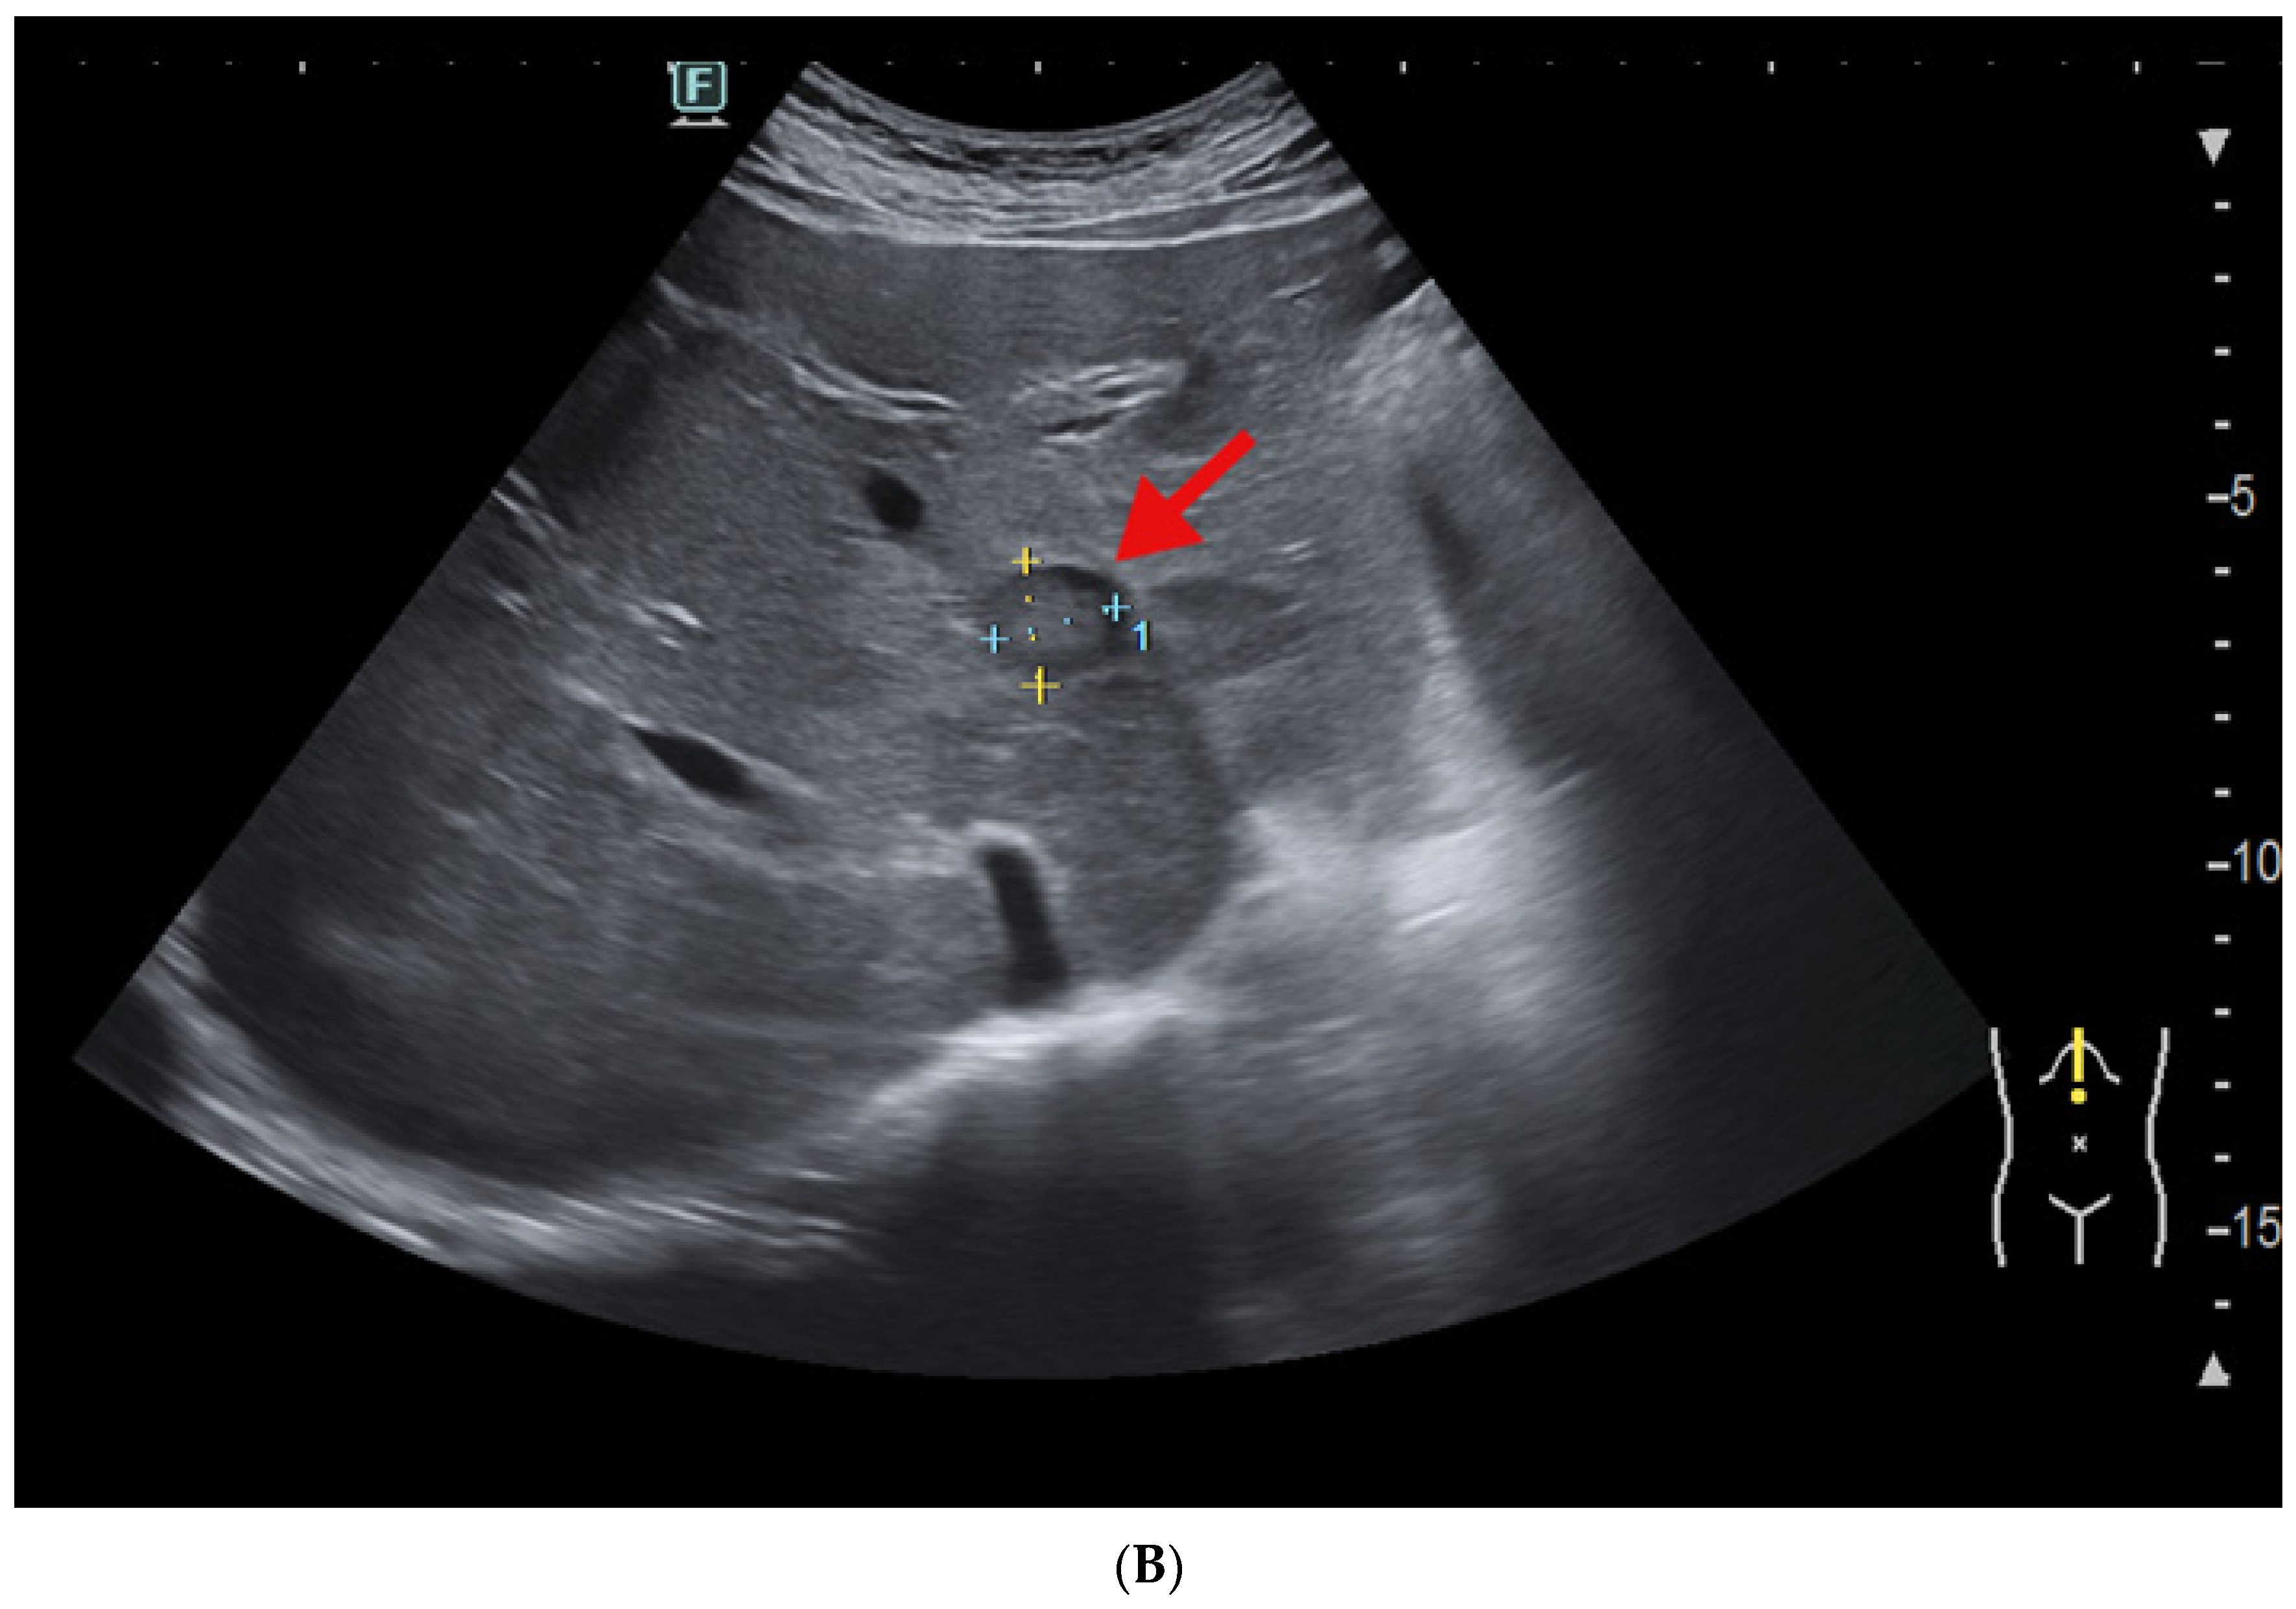

2.5. Imagery Scans